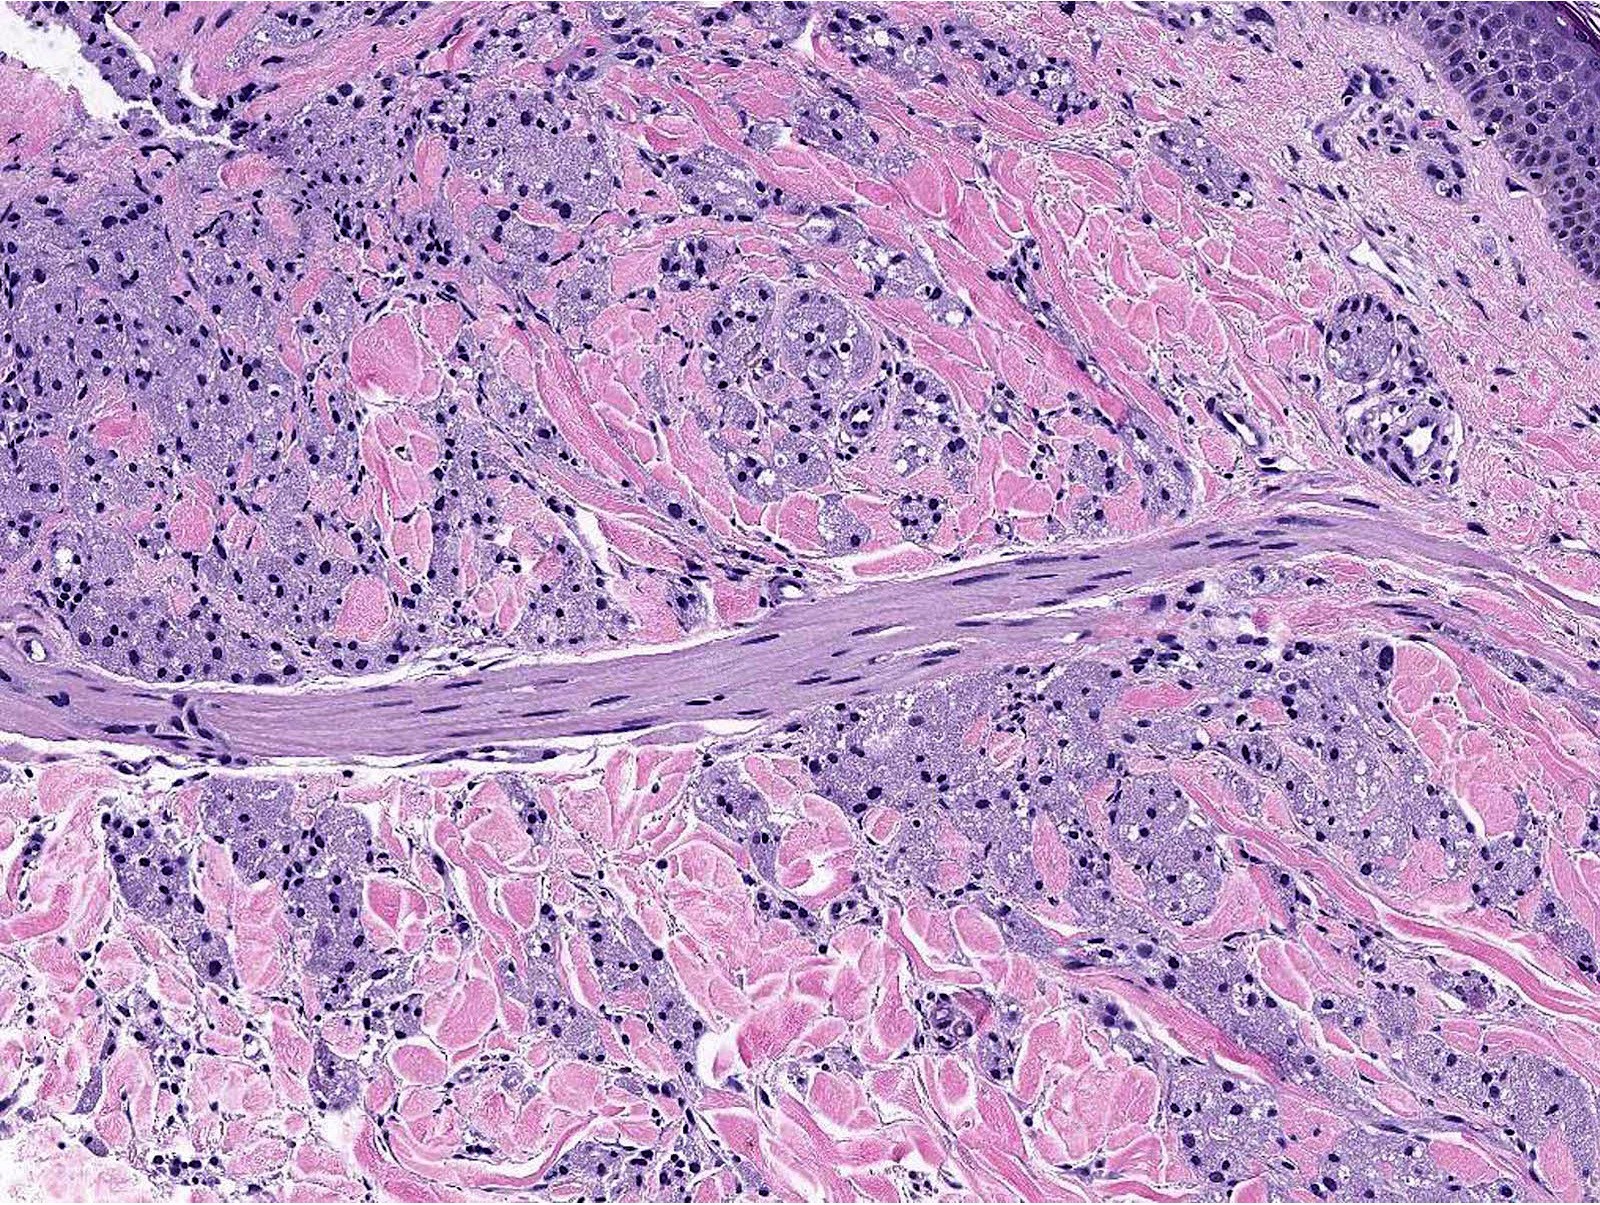

Microscopic (histologic) description

- Infiltrative or circumscribed architecture

- Can involve the subcutis

- Large polygonal cells with abundant eosinophilic granular cytoplasm and small, central nuclei

- Epidermis can show pseudocarcinomatous hyperplasia

- Lysosomal macroinclusions (pustulo-ovoid bodies of Milian) are usually present (J Cutan Pathol 2007;34:405)

- Can exhibit accentuation around arrector pili muscles or peripheral nerves (J Clin Pathol 2014;67:19)

- Nonneural granular cell tumors (S100-) can exhibit nucleomegaly, pleomorphism and variable mitotic activity (Am J Surg Pathol 1991;15:48, Histopathology 2005;47:179)

Microscopic (histologic) images

Contributed by Jarish Cohen, M.D., Ph.D.